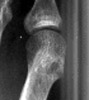

Gout: Erosions 1st MTP joint with preservation of joint space

+ ++